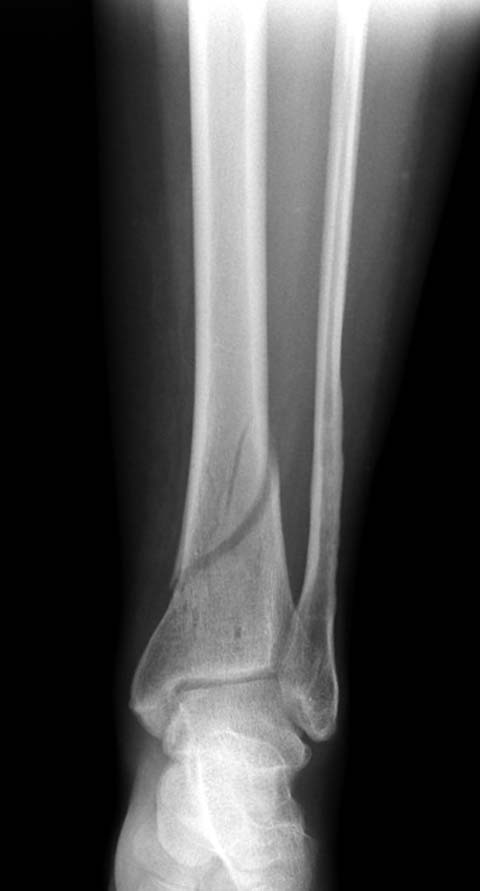

Первый случай, где перелом в результате падения с небольшой высоты, где мортиз рентген снимок показал отстутствие укорочения наружной

лодыжки и КТ срезы подсказали направления атаки. После такой фиксации нет надобности в гипсовой повязке, брейс и через две недели движения в

суставе без нагрузки.